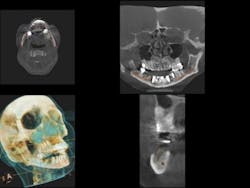

As practitioners work to meet the growing demand for implants, cone beam computed tomography (CBCT) is an essential tool for treatment planning and post-procedure monitoring. By providing highly accurate 3-D images of the patient's anatomy from a single, low-radiation scan, CBCT technology delivers a comprehensive understanding of the patient's jaw and the anatomical structures necessary to properly provide treatment (Berger et al.). (See Fig. 1)

The anatomy and health of the maxillary sinus are critically important during augmentation or subantral augmentation of this area. The more information a clinician has before addressing this region, the more predictable the results. (See Figs. 2a and 2b)